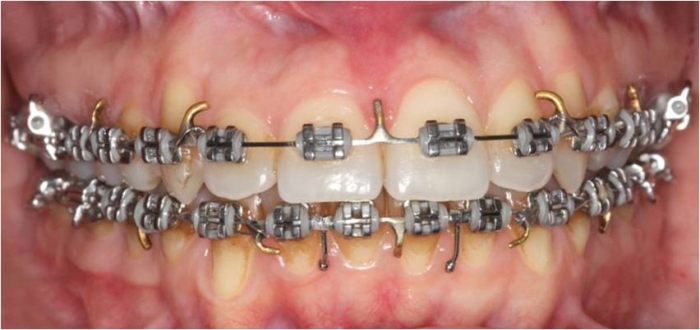

Mordida inicial